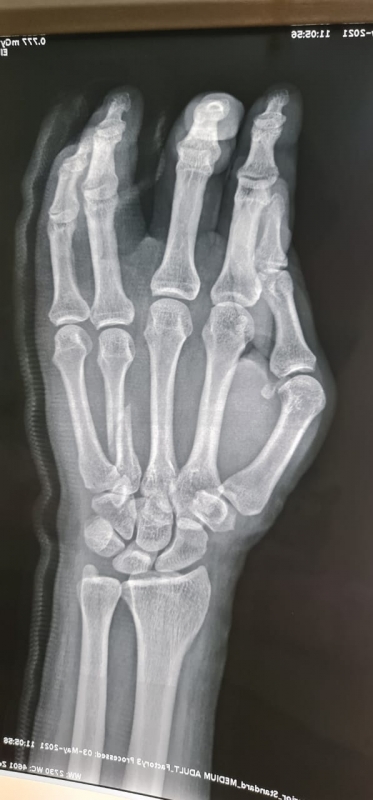

تمكّن فريق طبي متخصص بمستشفى حريملاء العام من إجراء تدخل عاجل وطارئ، للتعامل مع حالة لمواطن سعودي خمسيني مصاب بكسر متزحزح بالمشطية الرابعة لليد اليمنى إثر حادث سقوط.

واستقبل قسم الطوارئ بالمستشفى المصاب حيث تم على الفور تشكيل فريق طبي مكون من أخصائيين قسم جراحة العظام والكسور بالمستشفى، وقام الأطباء على الفور بعمل الإسعافات الأولية وإعطائه المحاليل والمسكنات والمضادات الحيوية، وتم عمل الأشعات العادية والمقطعية، التي أظهرت أن المريض يعاني من كسر متزحزح بالمشطية الرابعة لليد اليمنى ويحتاج تصليح مفتوح للكسر وتثبيت بشريحة ومسامير ذات طابع خاص، فتم نقل المريض إلى غرفة العمليات وإجراء عملية تثبيت بشرائح ومسامير.

الجدير بالذكر، أن هذه العملية تعتبر الأولى من نوعها التي تجرى بمستشفى حريملاء العام وتتمثل في عملية جراحة اليد التخصصية والتجميل.